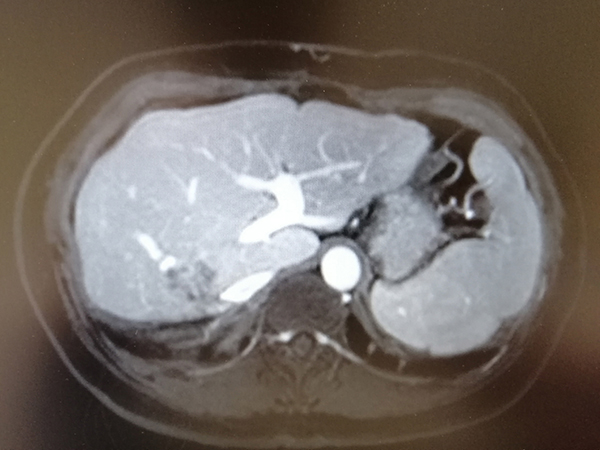

治療前